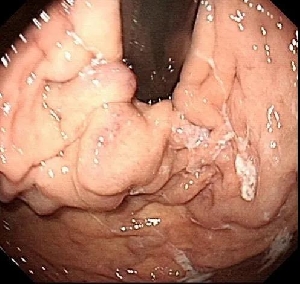

消化內(nèi)二科成功開展鈦夾聯(lián)合組織膠治療胃脾分流胃底曲張靜脈團術(shù)

患者李某,女,80歲,因黑便1周急診以消化道出血、重度貧血收治消化內(nèi)二科。入院后予禁食、抑酸、補液、輸血處理,與家屬溝通,完善胃鏡檢查,結(jié)果示胃底巨大曲張靜脈團、門脈高壓性胃病。蓋偉主任考慮胃底靜脈團大、靜脈壓力高,合并分流道的可能性越大,且多數(shù)為胃脾分流,應首先完善門靜脈血管成像檢查,以明確血管情況。